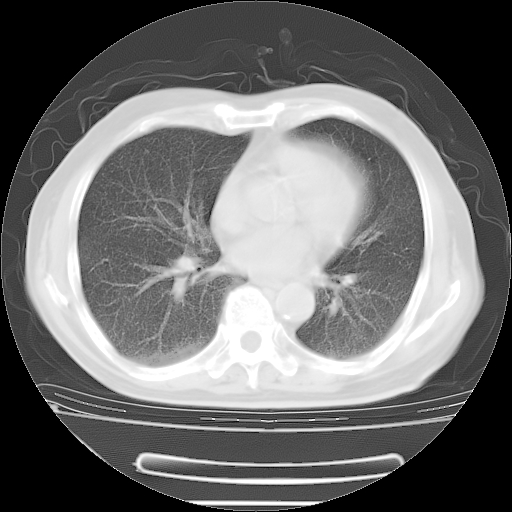

今天复查肺部CT,发现双肺广泛磨玻璃样改变。所以我把3月19日和5月9日相隔50天的肺部CT上传。请大家会诊。

2009年3月19日肺部CT片。

2009年3月19日肺部CT